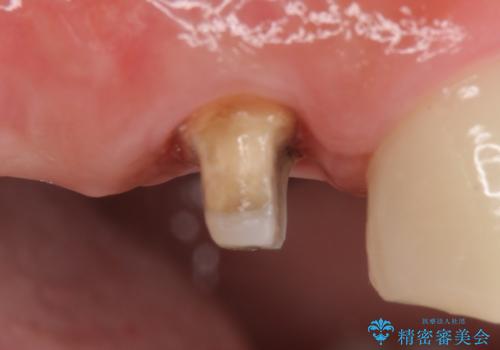

今回用いたオールセラミッククラウンはジルコニアフレームという白い素材の上にセラミックを盛っているため、審美性が非常に高いのが特徴です。

また、ジルコニアは人工ダイヤモンドの材料にも使われているほど高い強度を持っており、そのためオールセラミッククラウンは審美性だけでなく、奥歯やブリッジの補綴も可能とするクラウンです。